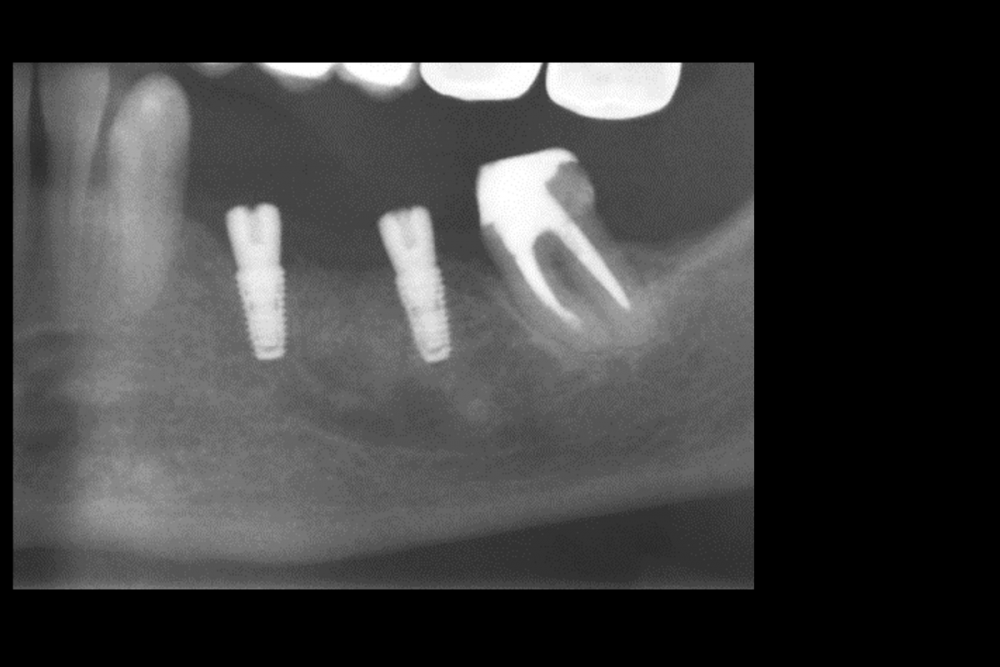

Карен Аванесов Опубликовано 11 февраля, 2022 Поделиться Опубликовано 11 февраля, 2022 все на слайдах. 2 Ссылка на комментарий

Карен Аванесов Опубликовано 11 февраля, 2022 Автор Поделиться Опубликовано 11 февраля, 2022 10 минут назад, Дмитрий Л. сказал: Прокомментируете? Имею опыт по таким методам "присыпки", результаты хорошие, но не впечатли Ссылка на комментарий

Bier Опубликовано 14 февраля, 2022 Поделиться Опубликовано 14 февраля, 2022 от подобной присыпки толку обычно нет. Ссылка на комментарий

Карен Аванесов Опубликовано 15 февраля, 2022 Автор Поделиться Опубликовано 15 февраля, 2022 13.02.2022 в 22:56, Fin сказал: Карен. Подскажите пожалуйста. Правильно ли я понял, что в на данный момент в такой ситуации (оголение импланта с вестибулярной стороны на половину) Вы бы обошлись просто установкой импланта + ССТ вестибулярно? Да, именно так. 14.02.2022 в 10:33, Bier сказал: от подобной присыпки толку обычно нет. Олег, помнишь аник "темно здесь..." Вот только не начинай про полужесткие сосиски)))) Но ты прав или делпать по отработанной технологии или никак 1 Ссылка на комментарий